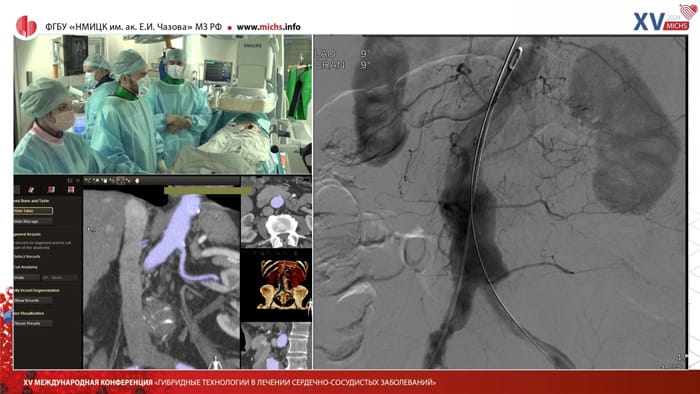

Представляем видеозапись сателлитного симпозиума Philips, который состоялся 06.02.24 в рамках MICHS-2024.   Спикеры: Имаев Т. Э, д.м.н., профессор, руководитель лаборатории гибридных методов лечения сердечно-сосудистых заболеваний ФГБУ "НМИЦК им. ак. Е. И. Чазова" Минздрава России;   Саидова М. А., д.м.н., профессор, руководитель отдела ультразвуковых методов исследования ФГБУ "НМИЦК им. ак. Е. И. Чазова" Минздрава России;   Лепилин П. М., к.м.н., старший научный сотрудник лаборатории гибридных методов лечения сердечно-сосудистых заболеваний ФГБУ "НМИЦК им. ак. Е. И. Чазова" Минздрава России.

Спикер: Лепилин Пётр Михайлович,  старший научный сотрудник лаборатории гибридных методов лечения сердечно-сосудистых заболеваний Института клинической кардиологии ФГБУ «НМИЦК им. ак. Е.И. Чазова» Минздрава России

Спикеры:  Лепилин П. М., к.м.н., старший научный сотрудник лаборатории гибридных методов лечения сердечно-сосудистых заболеваний ФГБУ "НМИЦК им. ак. Е. И.Чазова" Минздрава России д.м.н., профессор, руководитель  лаборатории гибридных методов лечения сердечно-сосудистых заболеваний ФГБУ "НМИЦК им. ак. Е. И.Чазова" Минздрава России

Имаев Т. Э.,